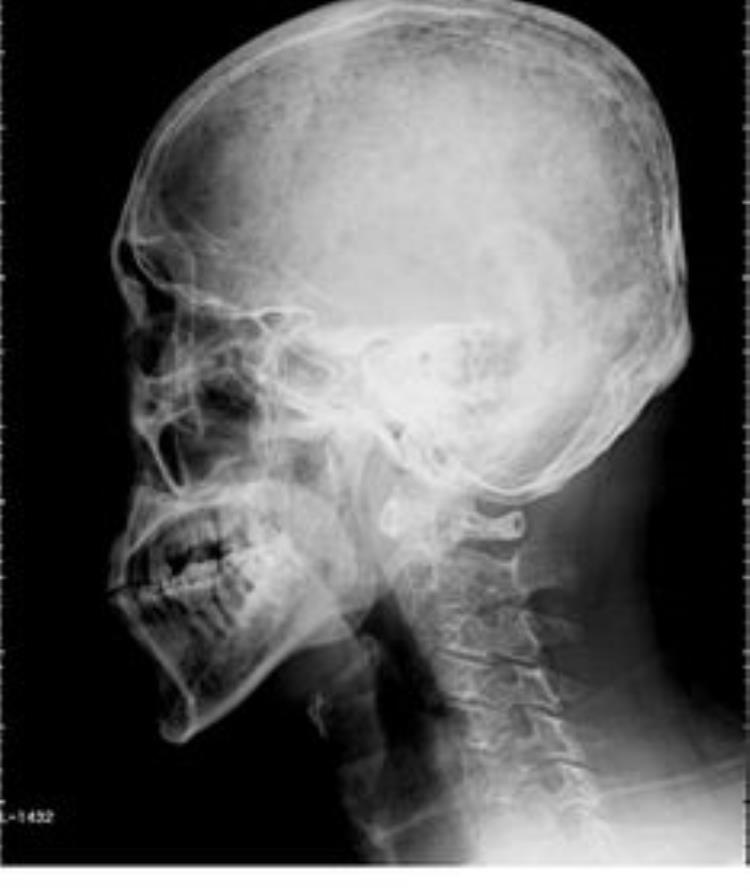

很多国际超模都是骨相美,有异于常人的气质和冷艳,正是面部匀称的肌肉和流畅的线条才有这番高级美感。苹果肌是骨相美女的一大特点,饱满的苹果肌和面部脂肪会看起来更年轻,面部骨肉匀称,即使上了年龄脸部也不会又干又瘪。线条流畅的脸型不管正面还是侧面,都棱角分明,饱满衔接。有这种特征的女人往往衰老的速度会比较慢,岁月很慢侵蚀她们的颜值!

不论是骨相美还是皮相美,比例协调都很重要,不然再好的五官条件也是白搭。一方面五官间的比较要协调,太过紧凑或太过分离都不好看,大众女神刘亦菲就是典型的皮相美和骨相美并存。另一方面是三庭五眼之间的协调,三庭是按竖向1:1:1的比例是标准的,五眼是面部轮廓横向以眼睛为基础,达到1:1:1:1:1的比例就是标准。这两方面都自然协调的面部,一般都长得很好看哦!

如果一个人的骨相好的话,那他的“皮相”再坏,也坏不到哪里去,而且会在整体上看来,会给人一个身材上的完美体现,这种美感,可是要远远超过那些只能够欣赏“大头照”的美人所不具备的。

而且,骨相好的人,还保证了即使是将来美人迟暮的时候,他也会有一个完美的骨架,协调的身姿,不会被年龄增大所带来的皮肤松弛等等问题所困扰,仍然会是一个“老美人”。